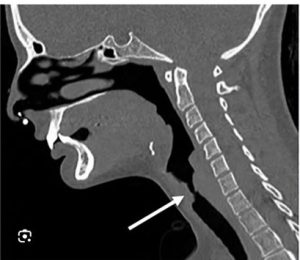

3 / 5

3. A patient presents with increasing shortness of breath and audible noisy breathing (stridor) following prolonged intubation. Flexible fiberoptic bronchoscopy reveals a subglottic stenosis where the tracheal lumen is visibly reduced to a small, pinhole opening, estimated to be less than 5% of the normal diameter, as shown in the image below. According to the Myer-Cotton Classification of subglottic stenosis, which grade corresponds to this finding?